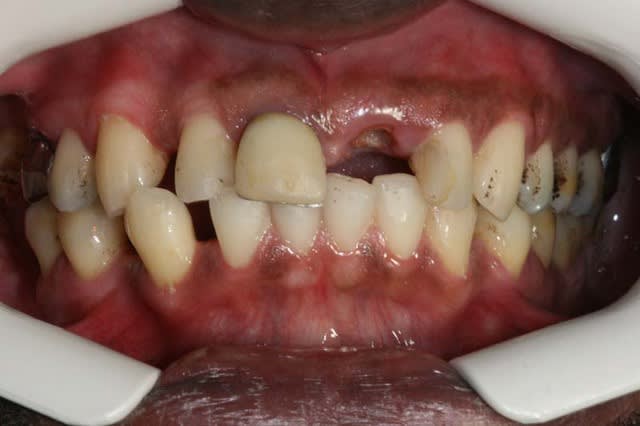

un correspondant m’envoie ce cas car la prothèse sur 21 se descelle tout le temps

il me demande si de l’ortho résoudrai le Pb.

sinon fais péter une photo de la CCM et une Radio de la dent siltipli...j'en discuterais avec Algi...;-)

Ton pote voudrait quoi? que tu redresse 13 /43?

Mauvaise posture/habitude linguale.

Faut voir les voies respiratoires supérieures.

Apnée du sommeil ?

L'occlusion est ''out'', mauvaise DV.

La 21, c'est la pointe de l'iceberg.

Ortho, oui, mais faut savoir où on va finir avant de commencer, sinon, c'est la récidive garantie.

Recoller la 21...c'est l'échec automatique.

j'ai oublié: 50 ans

je crois que son pote aimerait basiquement répondre à la demande du patient qui a changé de praticien, et qui aimerait remettre une prothèse sur 21 mais se demande bien comment gérer et a un pb de place:ou cela ne tiendra pas plus que les precedentes,ou elle va être en bout à bout très courte et très moche